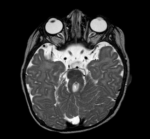

Gemeinsames pathognomonisches Kennzeichen ist das „Molar Tooth Sign“, welches sich als Folge der Kleinhirnwurmhypoplasie in der Magnetresonanztomographie findet.